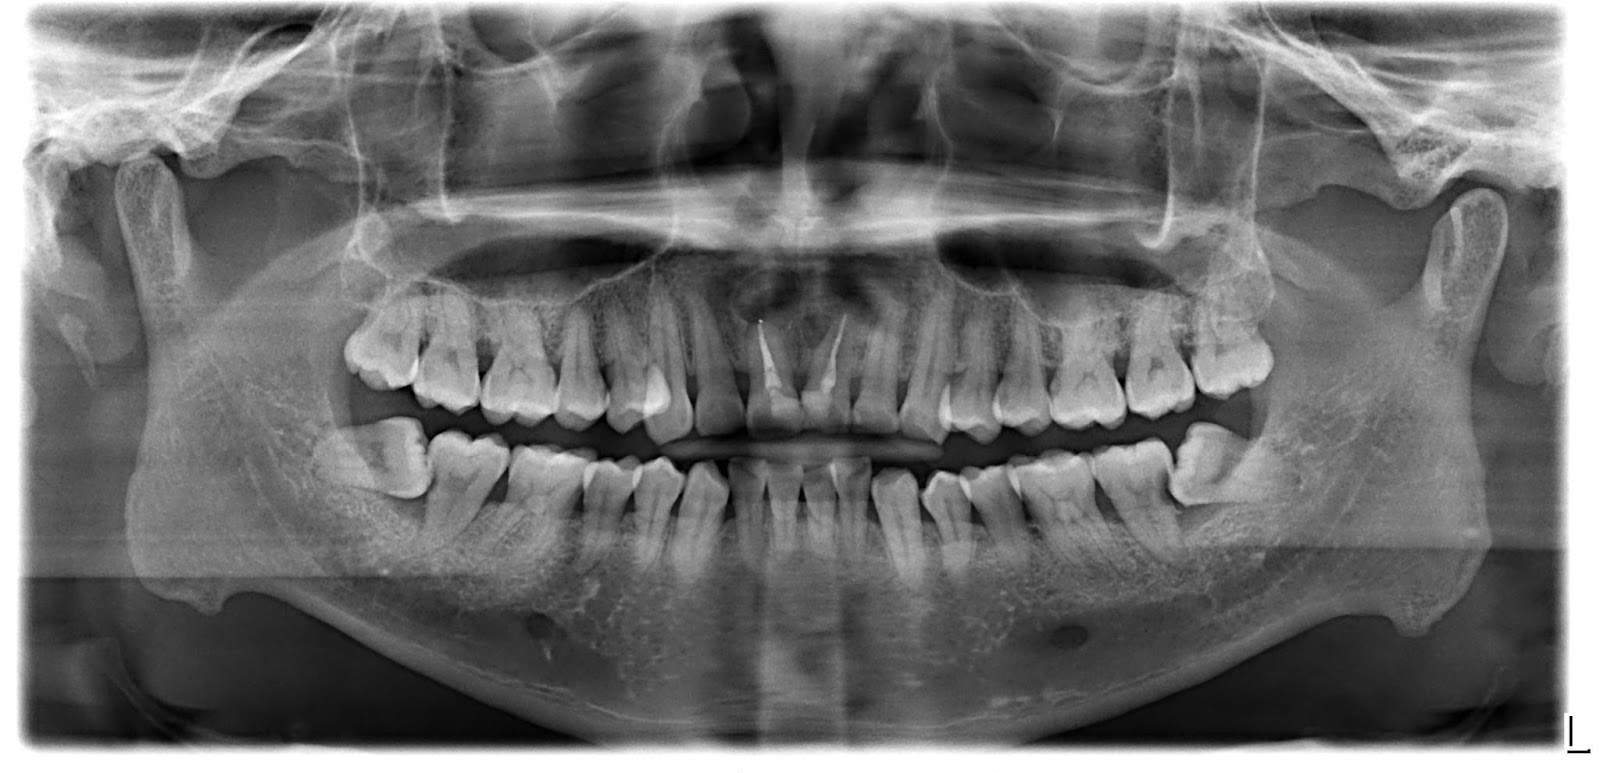

[建議圖片:展示杜牙根後的牙齒結構及牙根尖陰影的 X 光對比圖]

X 光異常:透過 X 光檢查發現牙腳附近出現陰影,通常代表根管再次受感染或牙齒斷裂。